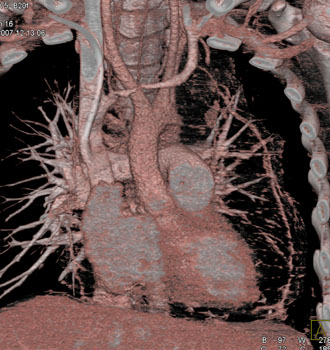

Question 6: 50ish yr old male with increasing SOB and dyspnea.What’s the diagnosis?

Diagnosis: Angiosarcoma of the Pericardium

• Most common cardiac sarcoma

• Most common in middle aged men

• Most commonly located near right atrial free wall with involvement of pericardium

• Typically infiltrates pericardium